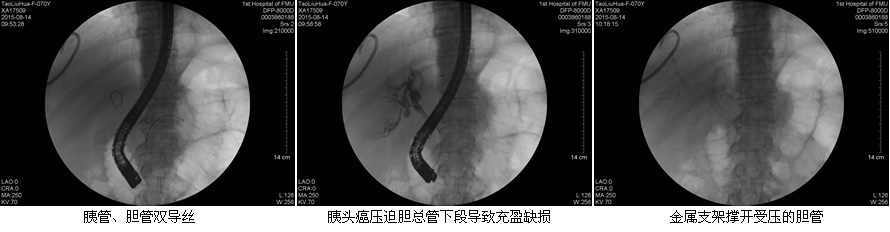

目前ERCP适应症主要包括:原因不明的阻塞性黄疸疑有肝外胆道梗阻者;疑有各种胆道疾病如结石、肿瘤、硬化性胆管炎等诊断不明者;疑有先天性胆道异常或胆囊术后症状再发者;胰腺疾病:胰腺肿瘤、慢性胰腺炎、胰腺囊肿等。在这50余例病例中,包含了内镜下乳头活检术、乳头括约肌切开取石术、胆管内支架引流术、鼻胆管引流术、“三镜”联合治疗胆总管结石等,患者术后无明显并发症发生,获得了良好的疗效,使我院ERCP诊疗技术进入一个崭新的时代。